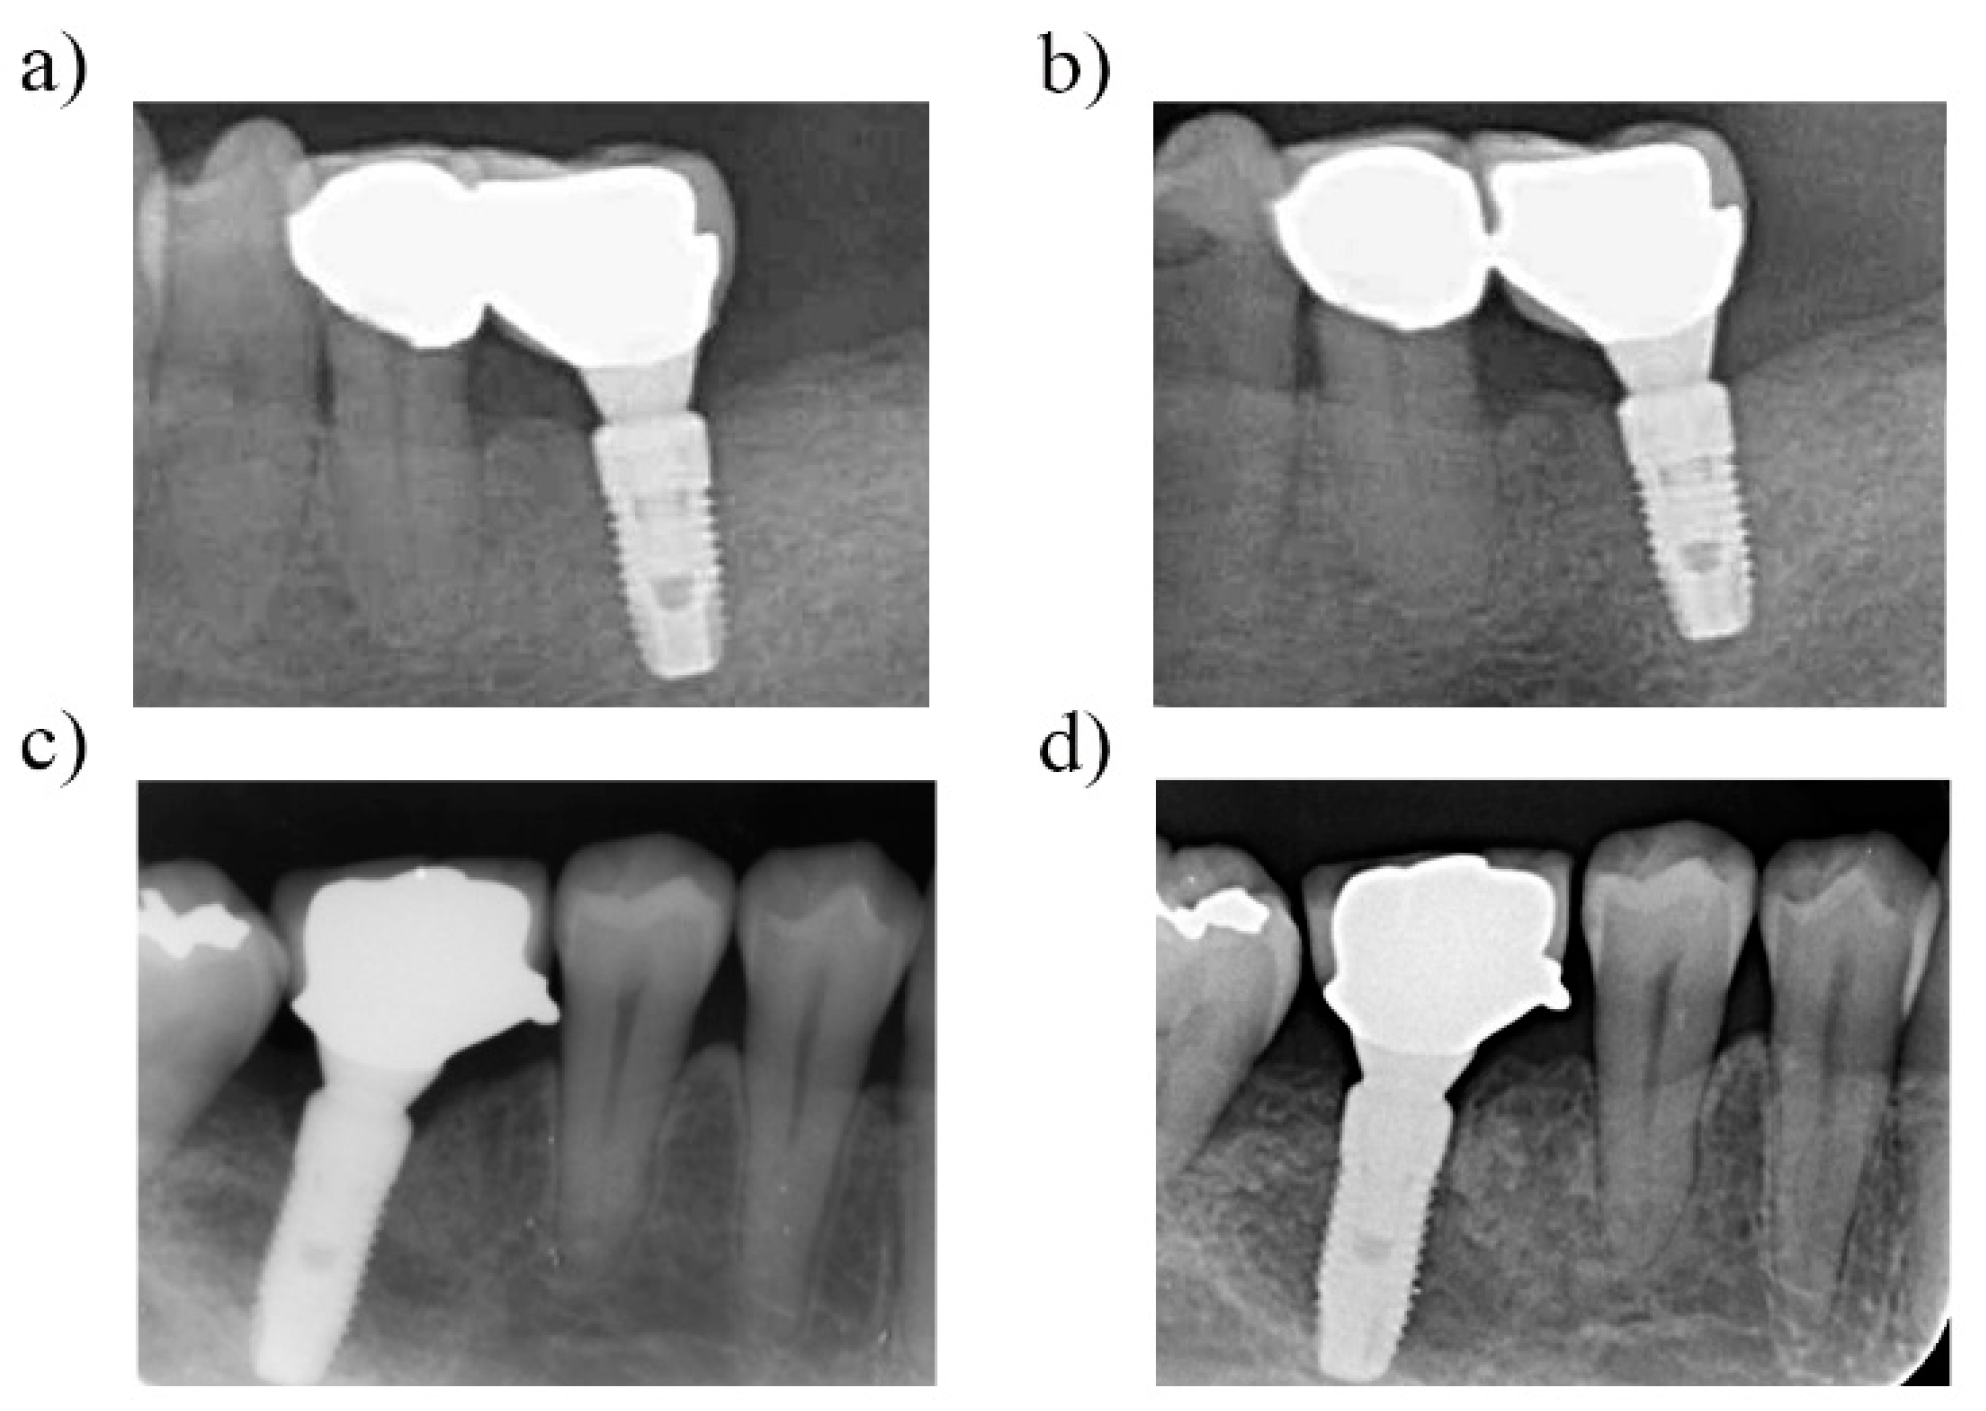

2.2. Surgical and Prosthetic Procedures